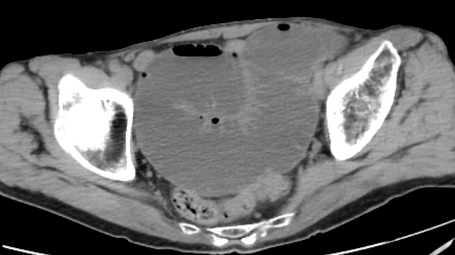

診断・検査方法

• CT検査